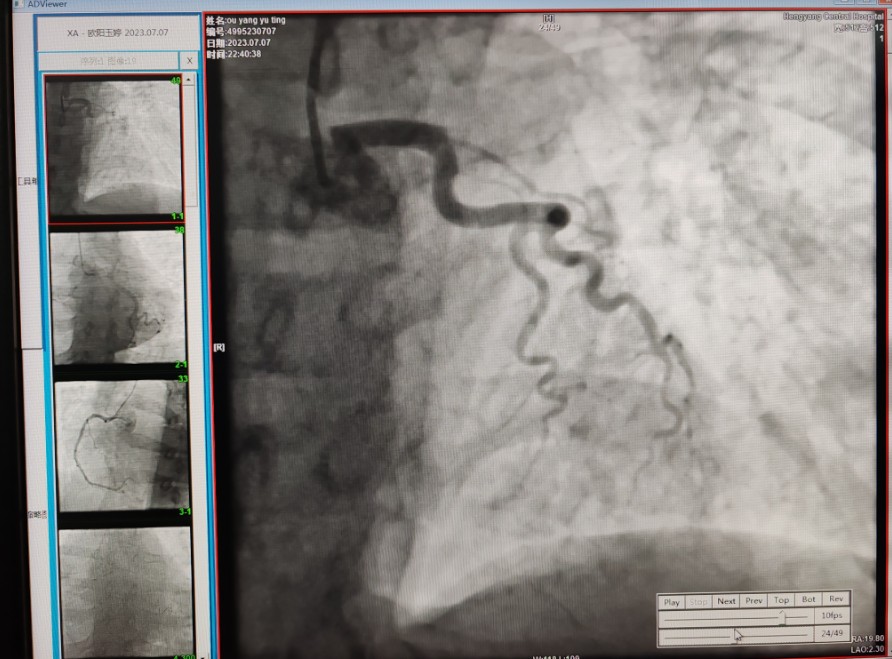

22:29分患者經(jīng)院內(nèi)綠色通道送達(dá)導(dǎo)管室,手術(shù)由雷剛副主任醫(yī)師主刀,楊繼賀副主任醫(yī)師為第一助手,介入技師及護士密切配合,聞訊而來的趙慶禧主任醫(yī)師坐鎮(zhèn)協(xié)調(diào)指揮。22:37分手術(shù)開始,冠脈造影顯示心臟上最重要的一條冠狀動脈-前降支開口齊頭閉塞,血管粗大且血栓高負(fù)荷,非??简灲槿胄g(shù)者的手術(shù)能力,一旦發(fā)生冠脈無復(fù)流或操作不慎血栓帶入回旋支導(dǎo)致循環(huán)崩潰,病人幾乎無生還希望;此時,患者手術(shù)臺上仍持續(xù)胸痛,且血氧飽和度在高流量吸氧狀態(tài)下不到80%,雷剛副主任醫(yī)師一方面指揮鎮(zhèn)靜鎮(zhèn)痛及抗心衰治療,一方面緊急啟用IABP(主動脈球囊反搏),然后精細(xì)操控細(xì)如發(fā)絲的介入導(dǎo)絲迅速通過病變,并予冠脈球囊擴張、冠脈內(nèi)溶栓、抗痙攣藥物使用、植入冠脈支架,最終成功開通“罪犯”血管,且無手術(shù)并發(fā)癥發(fā)生,整個過程張弛有度、快慢結(jié)合、一氣呵成?;颊咝g(shù)后胸痛明顯好轉(zhuǎn),血氧飽和度上升至96%,術(shù)后1天轉(zhuǎn)出監(jiān)護病房,第3天拔出IABP,目前已康復(fù)出院。